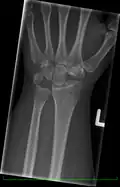

Radiographic classification

First described by David Lichtman et al. in 1977.[7] The purpose of this classification system is to guide treatment and to enable comparison of clinical outcomes.

1. Stage I Normal radiograph (possible lunate fracture).

2. Stage II Sclerosis of the lunate without collapse. (Portions of the lunate begin to deteriorate. This shows as a white blemish on x-rays.)

3. Stage IIIA Lunate collapse and fragmentation, in addition to proximal migration of the capitate.

4. Stage IIIB Lunate collapse and fragmentation, in addition to proximal migration of the capitate. In addition there is fixed flexion deformity of the scaphoid.

5. Stage IV Changes up to and including fragmentation, with radiocarpal and midcarpal arthritic changes.